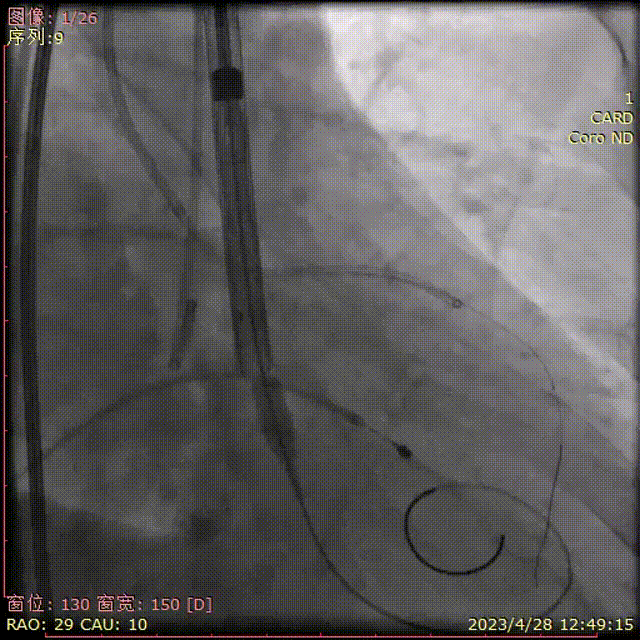

瓣膜初始定位

释放中确认位置

工作位多角度评估,位置可,冠脉灌注正常